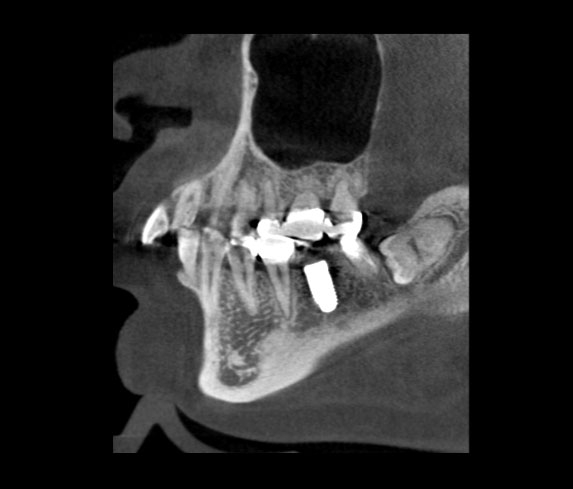

さて、先週の日曜日に千里ライフサイエンスセンターにて、ダイレクトボンディングのセミナーに参加してまいりました。

ダイレクトボンディングは、基本的なことは、保険のCR充填(コンポジットレジン充填)と変わることはありませんが、

使用する材料や、些細なことなのですが重要だったりするテクニックを学べて、非常に有意義であったと思います。

写真撮影・録音・録画禁止だったために写真は、隠し撮りさせていただいたこの一枚しかございません。泣デコメ絵文字